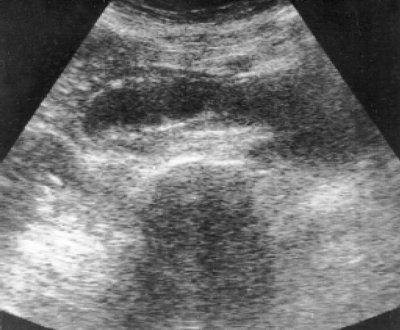

При УЗИ в печени патологических изменений не выявлено, желчные протоки и сосуды печени не расширены. Желчный пузырь увеличен в размерах - 10,4 x 4 x 6 см, стенки не утолщены, в нем определяется слой сгущенной желчи. Спустя 45 мин. после приема стандартного желчегонного завтрака отмечено незначительное сокращение желчного пузыря до 9,5 x 5,5 см. Поджелудочная железа смещена кверху и тесно прилежит к культе желудка. Размеры железы не увеличены, контуры местами нечеткие, вирсунгов проток не расширен, узловых и кистозных образований не выявлено. Кзади и ниже поджелудочной железы определяется полостное образование неправильной овальной формы величиной 13,6 x 4,8 см с наличием эхопрозрачного жидкого содержимого (рис. 1). При эхоскопии через различные промежутки времени размеры и форма образования, его содержимое даже после изменения положения больной оставались стабильными. Данное образование было расценено как "послеоперационная забрюшинная киста" и проведена пункция под ультразвуковым контролем. Эвакуировано 150 мл жидкости светло-зеленого цвета с наличием хлопьевидных образований. После пункции отмечено значительное уменьшение размеров "кисты" (рис. 2). Биохимическое исследование полученного содержимого: общий билирубин - 77,1, щелочная фосфатаза - 691, амилаза - 205, АЛТ - 28, АСТ - 23, рН - 7,0, белок не определяется, реакция на билирубин положительная. Микроскопия: билирубинат кальция в значительном количестве, множественные бактерии. Цитологическое исследование пунктата: клеточные элементы не обнаружены.

Рис. 1. Панорамная эхограмма брюшной полости в поперечной проекции. Отчетливо определяется полостное образование овальной формы с эхопрозрачным содержимым. Желчный пузырь (стрелка).